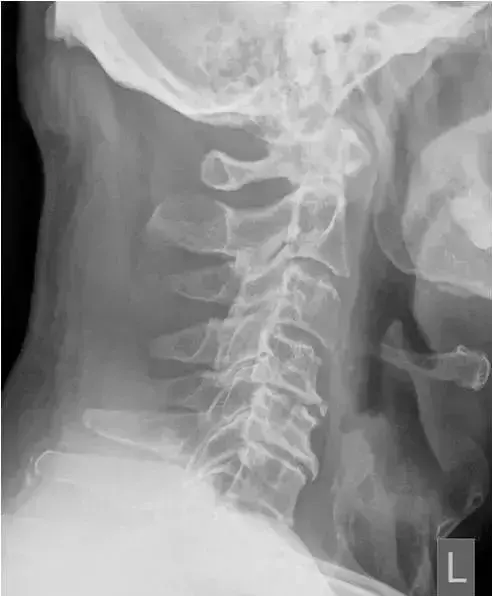

图2、正常的颈椎侧位片

图 6、颈椎生理曲度变直